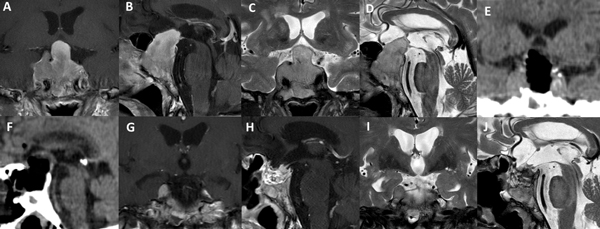

La técnica de “Guante Blanco” se indica en pacientes con macroadenomas no funcionantes, apoplejía pituitaria, enfermedad de Cushing, acromegalia, adenoma secretor de TSH y en portadores de prolactinomas con una clara indicación quirúrgica. La indicación principal es en tumores infradiafragmáticos, es decir, por debajo de la duramadre del diafragma selar o respetando el orificio del anillo dural (Figura 5). Se podría valorar a futuro su indicación en casos con extensión supraselar sin invasión ventricular y sin invasión lateral.

Existen situaciones que contraindican relativamente el uso de esta técnica y precisa un abordaje “extendido”: adenoma en reloj de arena, alto grado de extensión supraselar (e.g. invasión del III ventrículo), extensión para-selar (e.g. englobamiento carotideo), consistencia dura o fibrosa del tumor (Figura 6).

Figura 5. Paciente de 45 años con prolactinoma infradiafragmático resistente a cabergolina. Se utilizó un abordaje de Guante Blanco para su tratamiento. A-D: RM preoperatoria. E-F: TC del primer día postoperatorio. G-J: RM postoperatoria.

Figura 6. Paciente de 62 años, acromegálica, con adenoma gigante Hardy C y Knosp 4. No fue candidata a abordaje de Guante Blanco. Se utilizó un abordaje extendido para su tratamiento. A-D: RM preoperatoria. E-F: TC del primer día postoperatorio. G-J: RM postoperatoria.